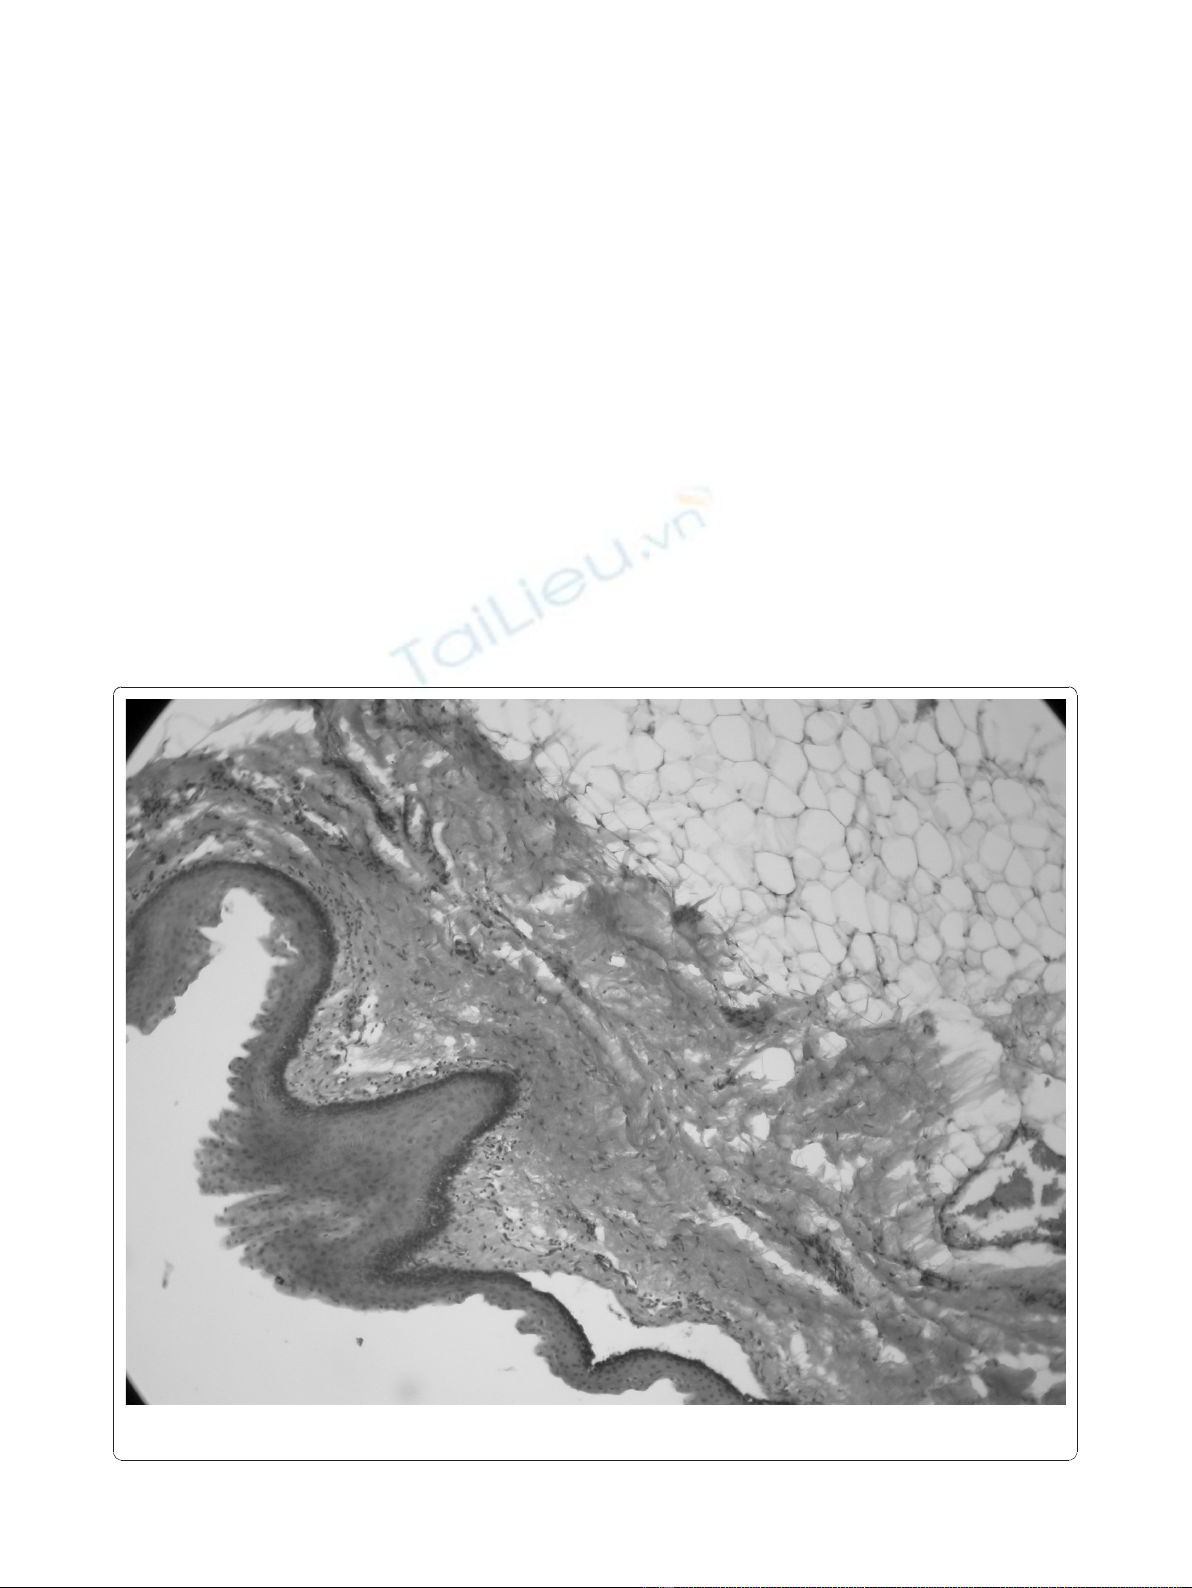

The lesion was excised completely. Histopathologic

examination of the mass revealed a variety of tissues

including skin, fat, connective and adipose tissue, and

vascular structures (Figure 3). A pathological diagnosis

of mature teratoma was made.

Figure 3 Variety of tissues including skin, fat, connective and adipose tissue, and vascular structures (haematoxylin and eosin, original

magnification × 40).